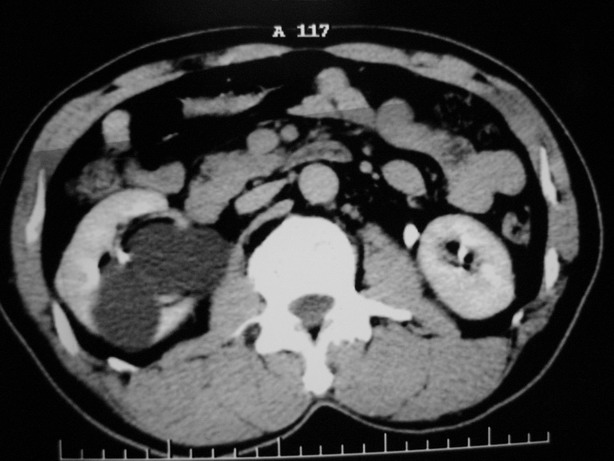

标题: CT10772:男性,48,右肾盂旁多囊性占位! [打印本页]

男性,48,体检发现,平时无症状。

肾盂旁多囊性占位,有实性成分,增强有轻度强化,收集期病变内无造影剂显影。诊断肾盂旁囊肿,有实性成分无法解释,查书后诊断为:多房性囊性肾瘤!!不知大家同意否?????????对本病知道不多,望大家不吝赐教!!

囊间间隔强化与肾实质相仿,还是支持多发囊肿,定期复查

支持多发囊肿(所谓实质部分其实是肾实质)

右肾多发囊性低密度影,囊内有增强的隔及实性组织,考虑囊性肾癌。